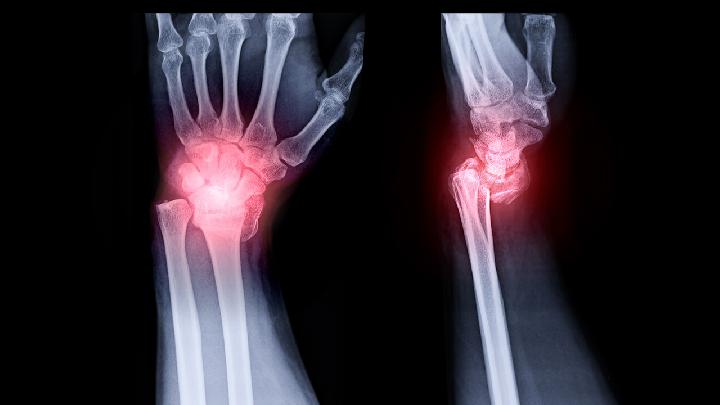

骨折